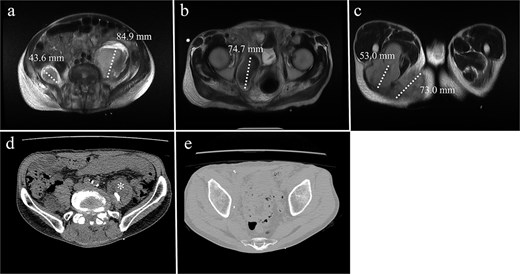

A 68-year-old male with a history of pelvic ring injury (fixation with two iliac screws 10 years prior) and degenerative lumbar spondylosis (spinal instrumentation 1 year prior) presented to the emergency department with fever and buttock pain. Magnetic resonance imaging revealed bilateral lobulated abscesses in the iliopsoas muscle (Fig. 5a–c). However, the abscess in the right psoas muscle extended caudally to the ischial tubercle and adductor muscles of the right thigh. Due to persistent fever with intractable pain in the right lower abdomen and right thigh, surgical debridement of the right psoas abscess was planned. The left psoas muscle was drained using a percutaneous CT-guided procedure because it was a solitary lesion.

MRI of a 68-year-old male with (a) bilateral psoas abscesses (right: 43.6 mm, left: 84.9 mm). The right abscess extended caudally to (b) the quadrilateral plate of the acetabulum and (c) the medial thigh and ischial tuberosity region. (d) Partial resolution of the right abscess with persistence of the left abscess (*). (e) Complete resolution of the right caudal extension after debridement.

The surgical procedure using the pararectus approach was similar to that used in Case 1. Surgical debridement was extended to the medial thigh and posterior buttocks (Fig. 6). Approximately 300 ml of pus was drained during surgical debridement. The bacterial culture yielded Streptococcus pyogenes. Serum CRP levels decreased progressively after surgery (Fig. 3). A repeat CT scan revealed a small residual abscess over the right iliac fossa with complete resolution of the infection of the left thigh and posterior buttocks (Fig. 5c and d). However, the resolution process was slow in the left psoas abscess treated with percutaneous drainage.